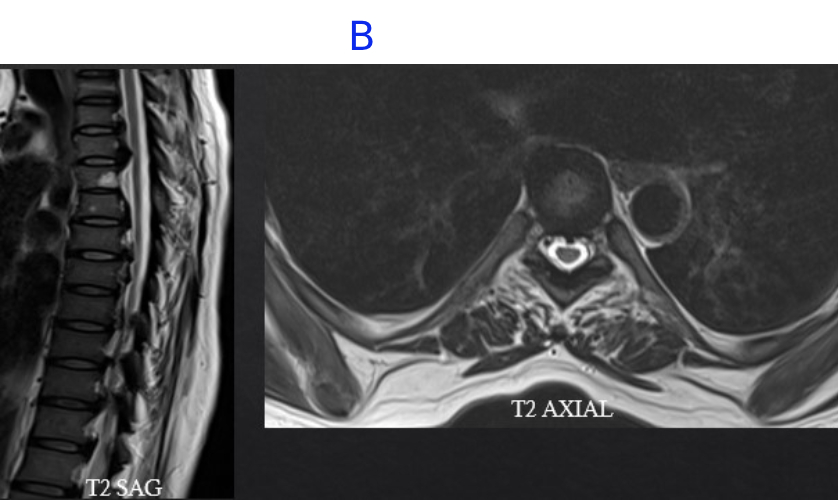

B) LEGENDS

• Multi-focal areas of posterior longitudinal ligament and ligamentum flavum hypertrophy at multiple vertebrae level indenting on the anterior and posterior thecal sac